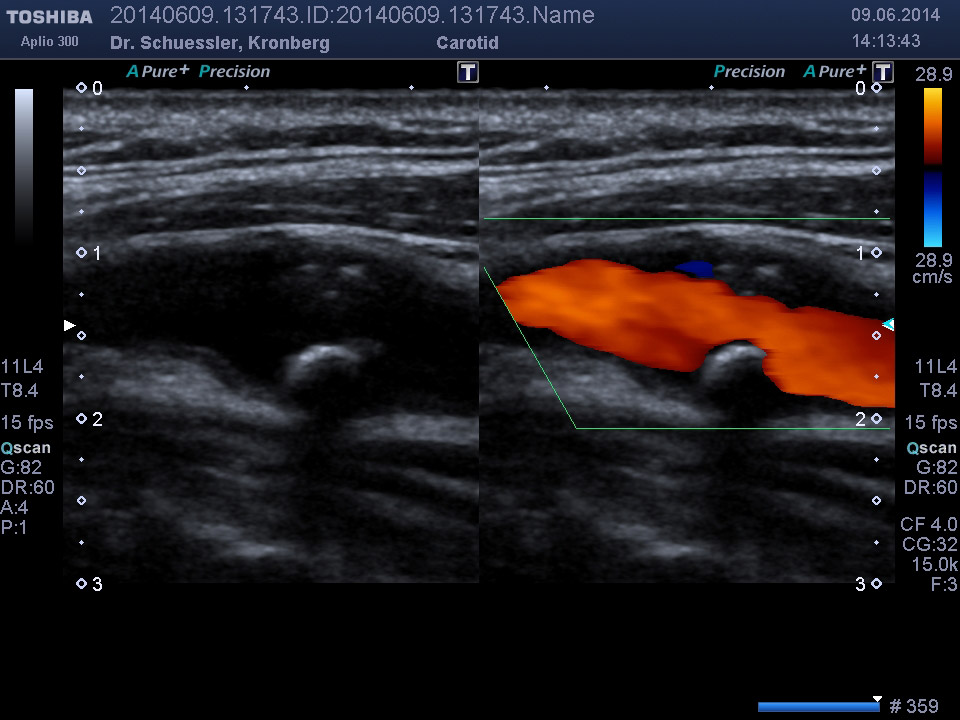

Die farbkodierte Duplexuntersuchung der Gefäße ist ein Ultraschallverfahren und gibt u.a. Auskunft über Verkalkungen, Einengungen, Verschlüsse oder Thrombosen im Bereich der Arterien und Venen.

Die Untersuchung wird angewandt zur Diagnostik von Verengungen in den hirnversorgenden Arterien, Erweiterungen (Aneurysmen) oder Verengungen der Bauchschlagader, Verengungen der Nierenarterien bei Bluthochdruck,  Venenthrombosen und zur Bestimmung des Gefäßrisikoprofils.